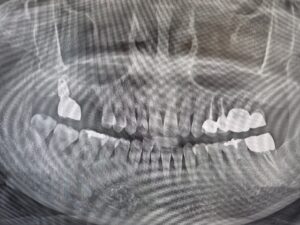

◆ 전 > 후 ◆

치료 마무리 후 환자분께서는

잇몸병으로 인해 입 냄새가 나고

식사도 편히 하지 못했던 이전과는 달리,

지금은 편안하게 식사를 하고

일상생활도 훨씬 자신감 있게

할 수 있게 되었다고 말씀해 주셨습니다.